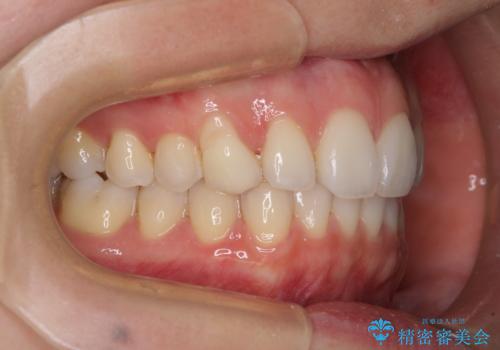

- 前歯のクロスバイトや残存している乳歯を気にして来院された患者様です。

上顎骨の幅が下顎骨よりも小さいので、拡大装置により骨幅を広げて上下関係を改善し、その後インビザラインにて歯並びを整えることとしました。

上下の骨幅を改善したことで、スムーズに歯列矯正を行うことができました。